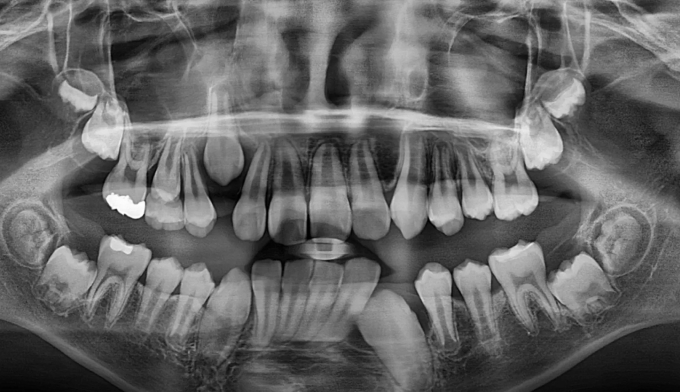

본 케이스에서는 위쪽과 아래쪽 송곳니 모두 치아 머리 주변으로 작은 물혹이 감싸고 있어 스스로 구강내로 나오지 못하고 있었습니다.

간단히 해당 위치를 절개 후 물혹을 제거해주고 치아를 제 위치로 이동시켰습니다.

총 교정기간은 13개월입니다.